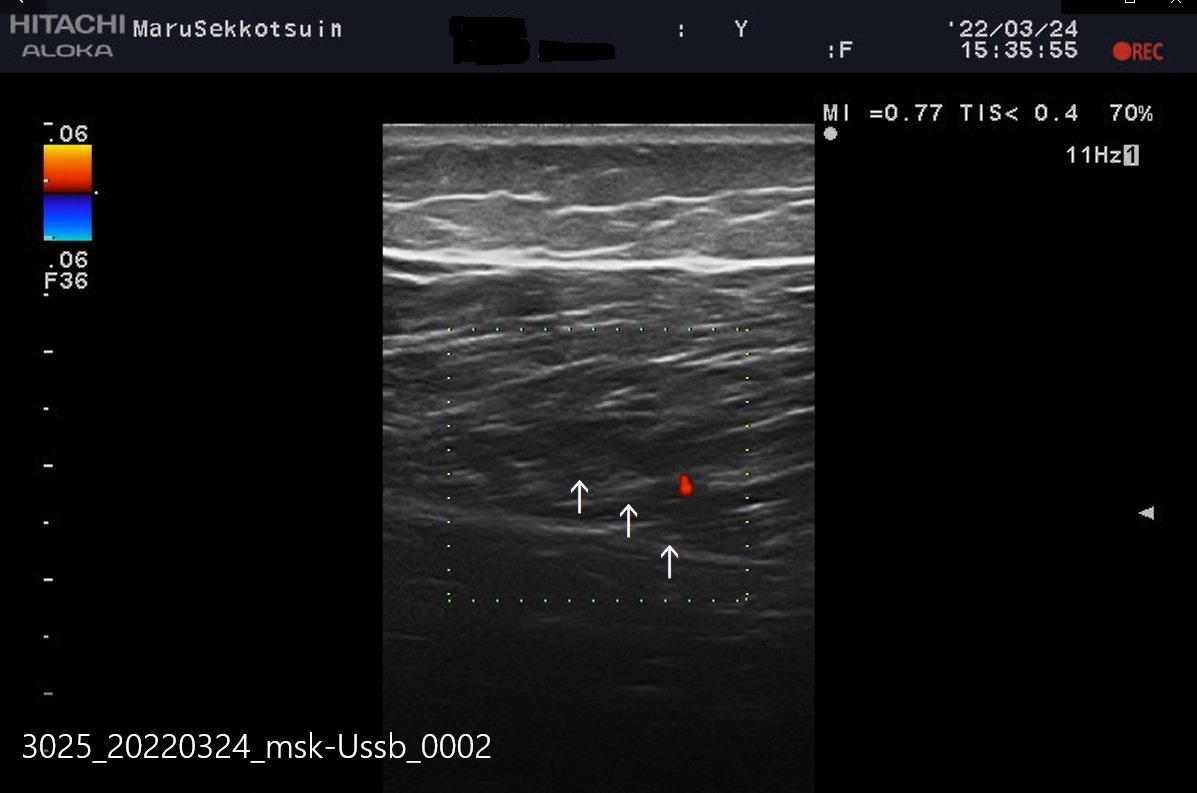

よ~く問診後、ストレステストを行い、圧痛点を探し、確認の為、エコー検査。

結果、半腱様筋部に損傷部位を確認し、軽度ですが「ハムストリングスの肉離れ」と確定。

ハムストリングスの肉ばなれ.jpg